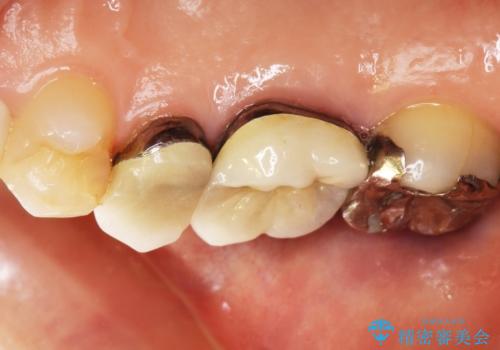

- 右上の奥歯がしみるとのことで確認すると、右上の一番奥の歯の銀歯の下が虫歯になっていました。

かなり大きな銀歯が装着されていたので、かぶせ物にて治療を行うこととなりました。

同時に右上の後ろから3番目の歯のかぶせ物も適合が悪かったので同時に治療することとなりました。